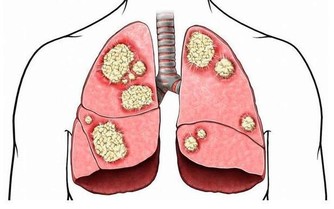

演變成肝癌的過程,是有著一個三部曲,那就是肝炎、肝硬化、肝癌的這樣子一個過程。其中,引起肝癌的誘因還有黃曲霉毒素,由於特別容易被忽視,尤其是在廚房裡面,那就需要特別引起人們的注意。

黃曲霉毒素是一種特別容易致癌的物質,能夠對人體內的肝臟組織造成一定的破壞,嚴重的情況下會導致肝癌甚至是死亡。廚房裡面的花生米還有玉米是最容易被黃曲霉毒素污染的食物,因為裡面是含有澱粉的成分,由於在運輸的過程中,遇到了潮濕還有發霉的情況,就會直接導致出現被黃曲霉毒素污染。及時是經過油炸或者是加熱的過程,也是很難能夠去除掉黃曲霉毒素。

還有,被黃曲霉毒素污染的食用油,我們會聞到有一種“哈喇油”的味道,這個時候,一定要把食用油扔掉,不然的話食用之後,就會大大增加患癌的風險。

有的人就以為,黃曲霉毒素經過了高溫殺滅之後就會沒事。其實,這是一個錯誤的想法。在我們平時做飯的時候,一般的溫度都不會超過在100℃,然而黃曲霉毒素需要經過260℃之後才能夠進行降解,因此我們在平時做飯的時候是很難能夠將黃曲霉毒素進行消滅掉。

除了廚房裡面的食用調料容易產生黃曲霉毒素,還要注意食用的餐具也是很容易會被污染。例如就是小筷子,時間一長了,就會有出現裂縫和小毛刺之類的東西,如果清洗不干淨,難免會有一些殘留物在筷子的上面,這樣子食物就會逐漸地發霉,這樣子的情況下就特別容易會滋生黃曲霉毒素。長期下來,對肝臟的健康造成一定的威脅,大大是加重肝病的發病率。